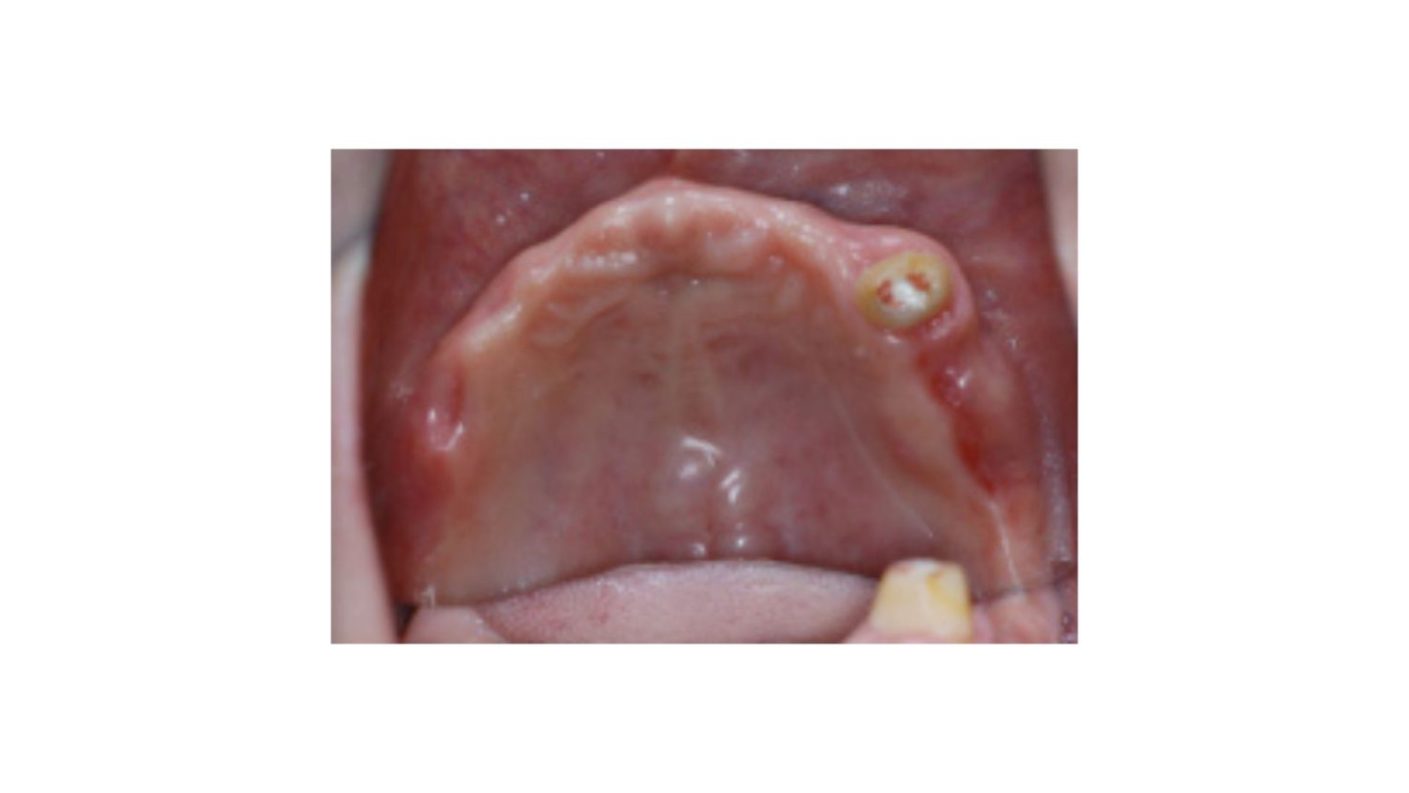

多数歯欠損のインプラント治療の症例(うえだ歯科)

| 主訴 | 歯がグラグラで噛むことができない。インプラントをして欲しい。 |

| 治療内容 | 歯周病で骨の吸収が重度で保存不能なため抜歯、仮の入れ歯を作り、6ヶ月の抜歯窩の治療の後に、インプラントのCTによる診査診断を行い、下顎に6本インプラント埋入と同時に仮歯を入れる。その後、上顎は8本のインプラント埋入と同時に仮歯を入れる。左右上6はソケットリフトによる上顎洞拳上術を行う。その後免荷期間6ヶ月待ってセラミックを用いた上部構造作製、装着しメンテナンスに移行する。 |

| 治療費 | 9,000,000円(税込) |

| 治療期間 | 2年3ヶ月 |

| 治療回数 | 90回 |

| 想定されたリスク | 重度の歯周病により無歯顎になったため、プラークコントロール不良による、術後のインプラント周囲炎が懸念される。歯冠の部分はセラミックなため欠ける可能性がある。 |